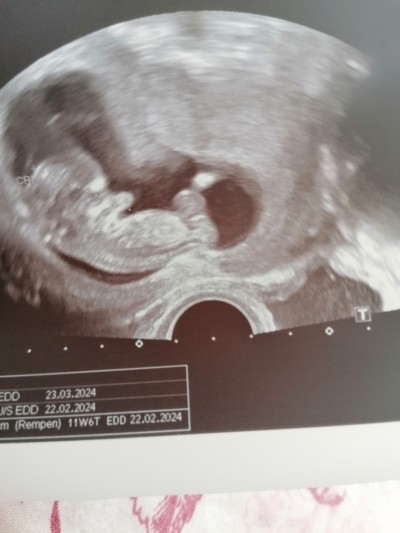

Kızlar cinsiyeti çok merak ediyorum ama doktor söylemedi yarın 13 haftalık olacam resime bakıp anlıya varmi

Gebelik haftası 12+6